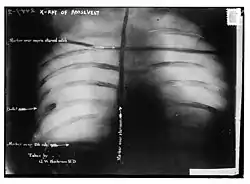

Afterwards, probes and an x-ray showed that the bullet had lodged in Roosevelt's chest muscle, but did not penetrate the pleura. Since doctors concluded that it would be less dangerous to leave it in place than to attempt to remove it, Roosevelt carried the bullet with him for the rest of his life.

Afterwards, probes and an x-ray showed that the bullet had lodged in Roosevelt's chest muscle, but did not penetrate the pleura. Doctors concluded that it would be less dangerous to leave it in place than to attempt to remove it, probably remembering what had happened to Roosevelt's immediate predecessor who died after the bullet's wound got infected, and Roosevelt carried the bullet with him for the rest of his life.[16][17] In later years, when asked about the bullet inside him, Roosevelt would say, "I do not mind it any more than if it were in my waistcoat pocket."[18]